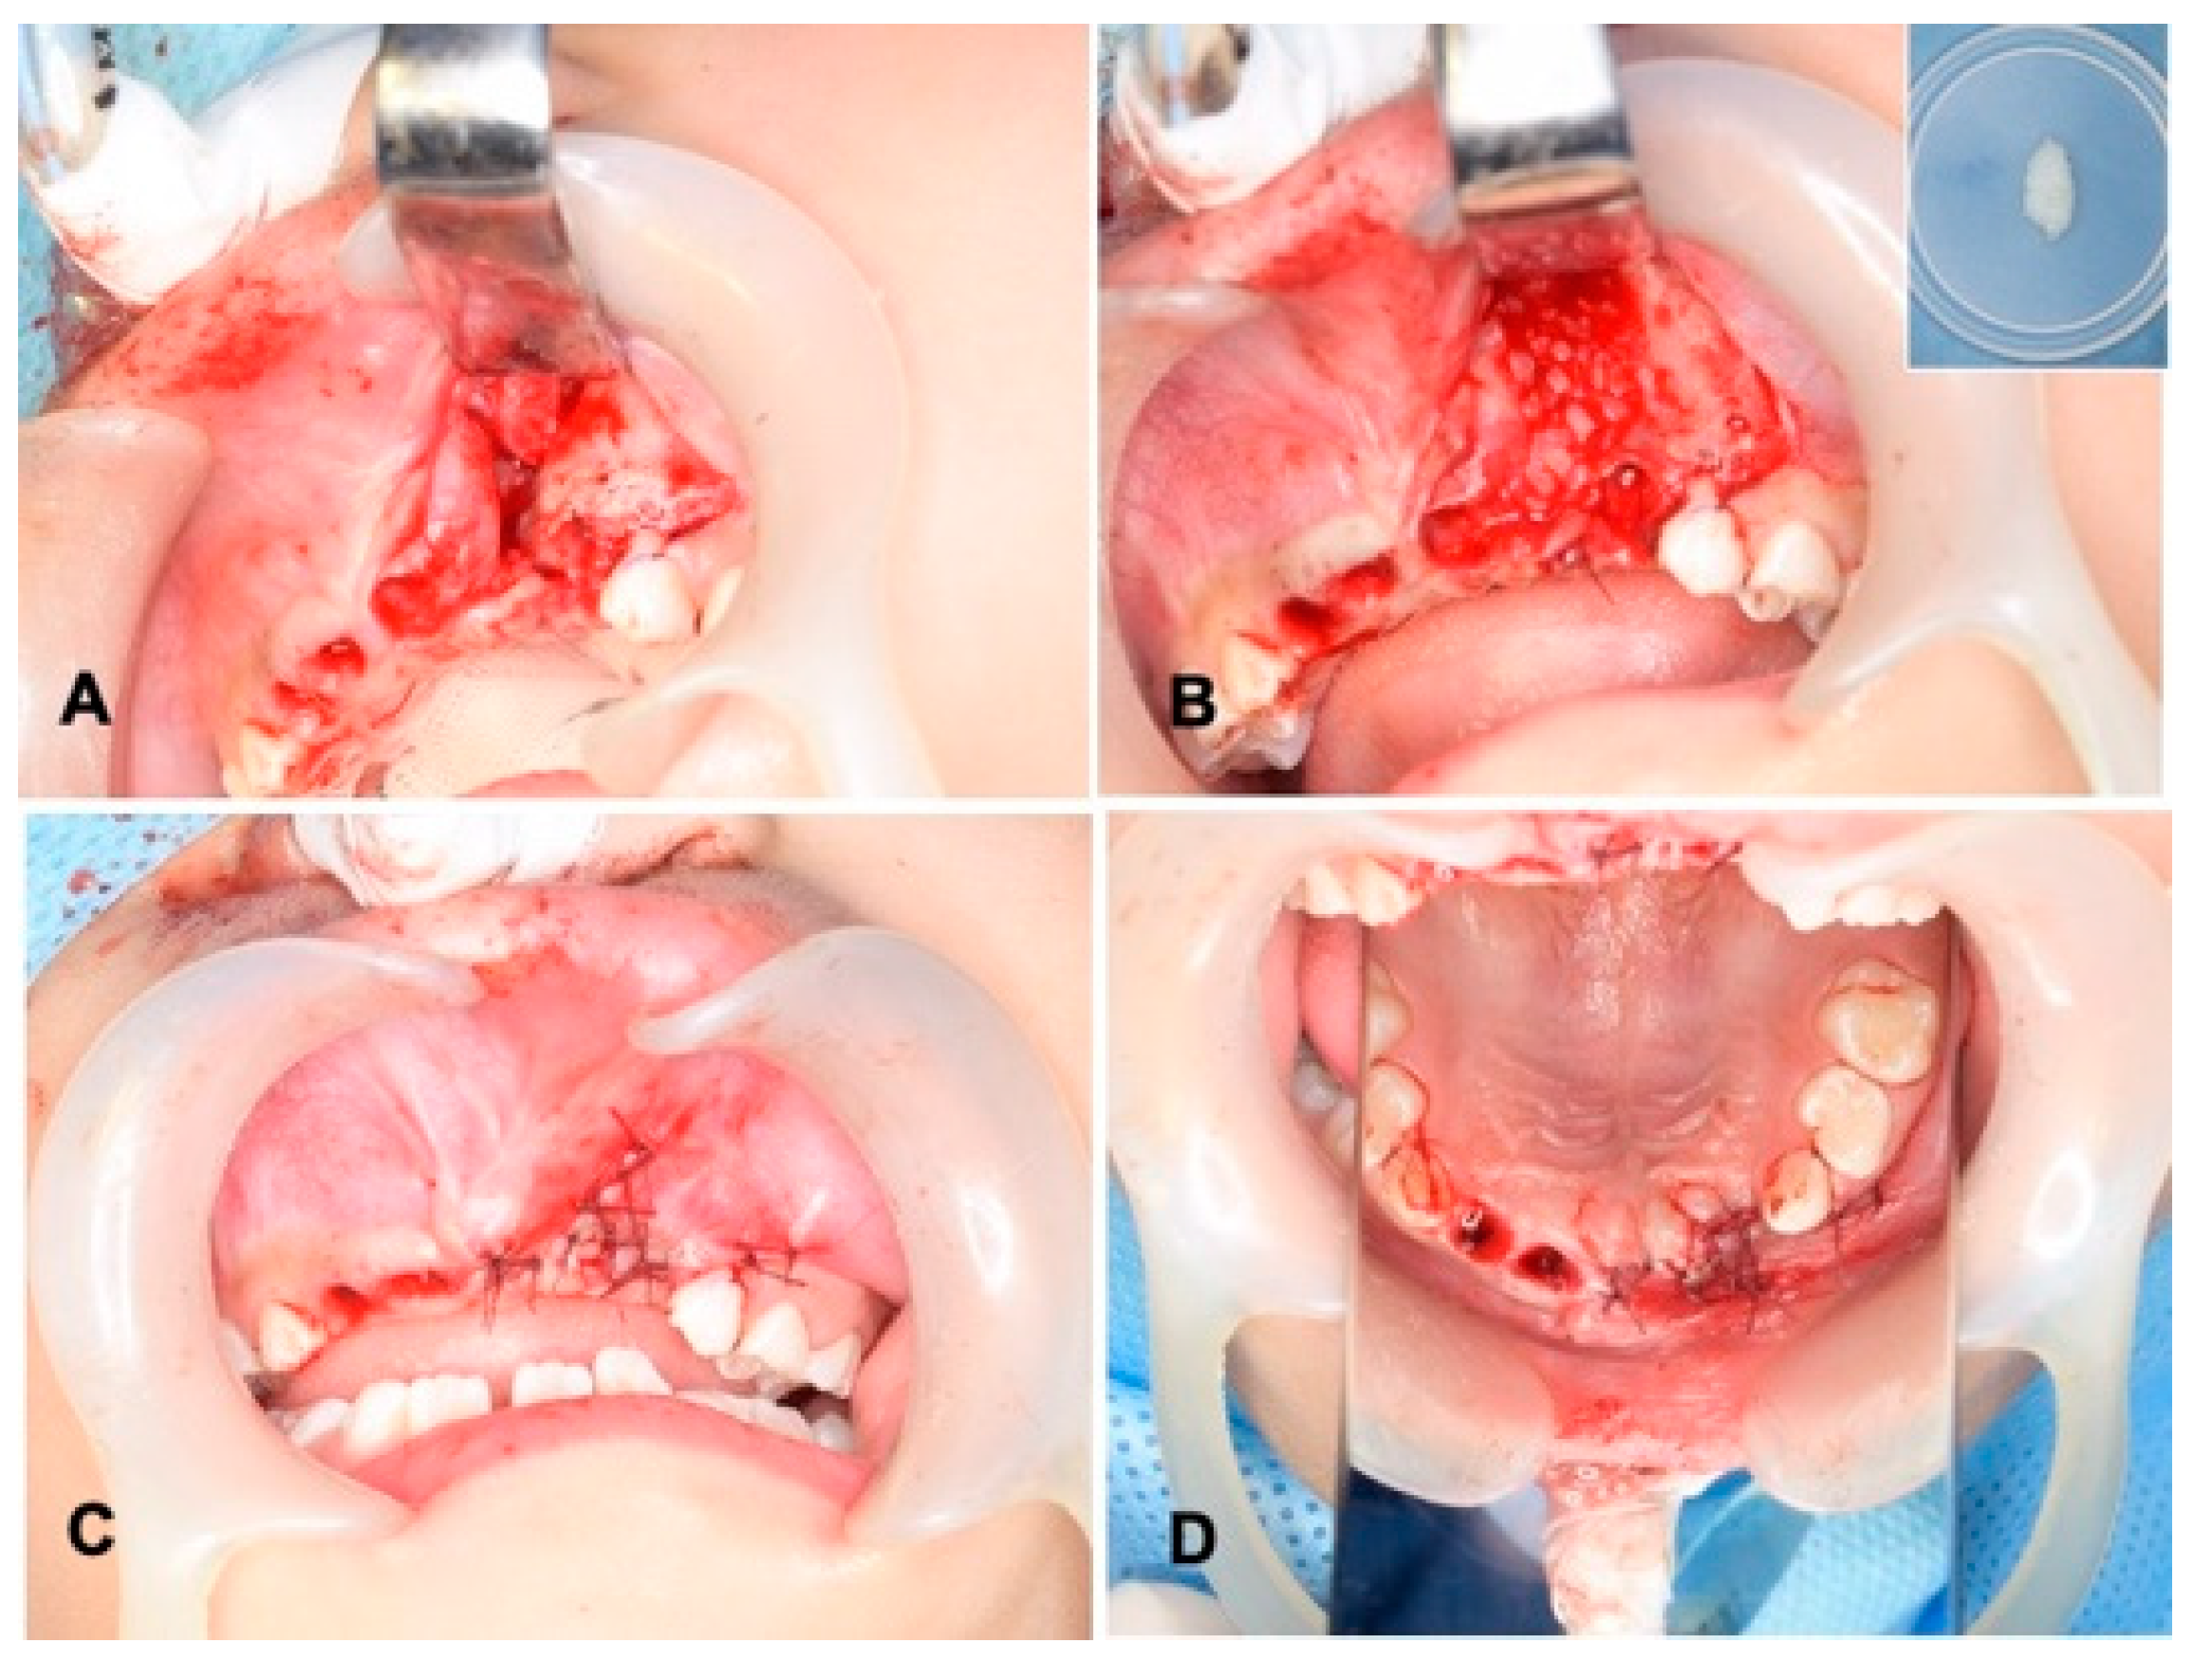

Figure 3.

Surgical procedure. (A) Exposed alveolar triangle defect and extracted sockets. (B) DDM graft after graft-bed management (closure of nasal lining with mucoperiosteum). Right upper: DDM granules. Note: DDM and blood coagulation. (C) Flap repositioned and sutured with absorbable threads. (D) View of mirror image.

2.4. Surgical Procedure of Unilateral Alveolar Cleft and Autograft of DDM

Wide exposure of the cleft area was achieved through incisions. The nasal mucoperiosteum was pushed upwards above the apices of the permanent central incisor adjacent to the cleft. The nasal and palatal openings were closed by suturing the mucoperiosteum on both sides of the cleft with absorbable threads (5-0 Polysorb®; Covidien, Mansfield, MA, USA) (Figure 3A). The wet DDM granules were grafted into the cleft triangle space (Figure 3B), and the labial flap was repositioned and sutured with the same absorbable threads (Figure 3C,D). The surgical time including the preparation of DDM was 74 min. The wound area was covered with a sterilized gauze including antibacterial ointment (bacitracin: BC), and it was protected by a custom-made acrylic plate for 1 week. The patient took antibiotics as follows: cefazolin sodium (CEZ: 500 mg, 2 times/day) for 2 days and then amoxicillin (AMPC: 6 g, 3 times/day) for 3 days.